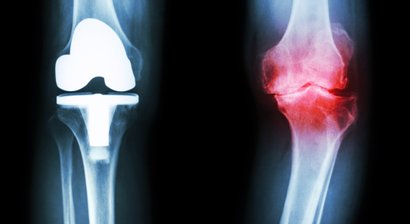

Knieprothese

Bei Patienten mit stark fortgeschrittener Arthrose im Bereich des Kniegelenks (Gonarthrose), bei welchen konservative Behandlungsmethoden zur Linderung der Schmerzen und Beschwerden nicht mehr wirksam sind, ist die Implantation einer Knieprothese sinnvoll, mit deren Hilfe das Kniegelenk wieder in ei...